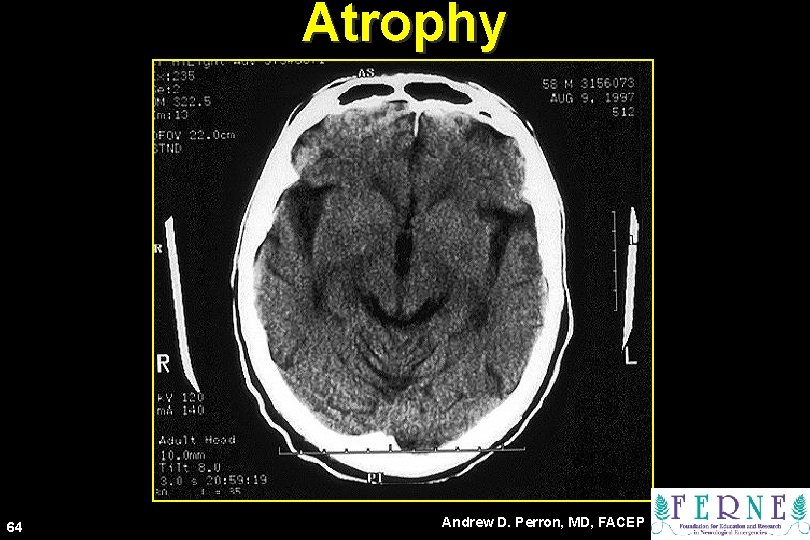

Atrophy 64 Andrew D. Perron, MD, FACEP